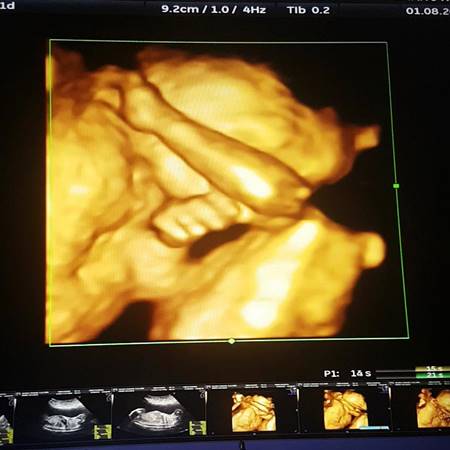

แอนดี้ เขมพิมุก โพสต์รูปภรรยาสาวท้องแก่ใกล้คลอด เผยเพศ ได้ลูกชายตั้งชื่อน้องอองเดร์ อย่างที่ตั้งใจไว้

หลังจากที่หนุ่ม แอนดี้ เขมพิมุก ได้ออกมาเปิดเผยว่า ภรรยาสาวนอกวงการได้ตั้งท้องแล้ว โดยถ้าเป็นลูกชายก็จะให้ชื่อ อองเดร์ ถ้าเป็นผู้หญิงก็จะชื่อ แอนเดรียน่า นั้น [อ่านข่าว : แอนดี้ เขมพิมุก เฮลั่น ภรรยาท้อง 3 เดือน จะได้เป็นคุณพ่อแล้ว ! คลิก]